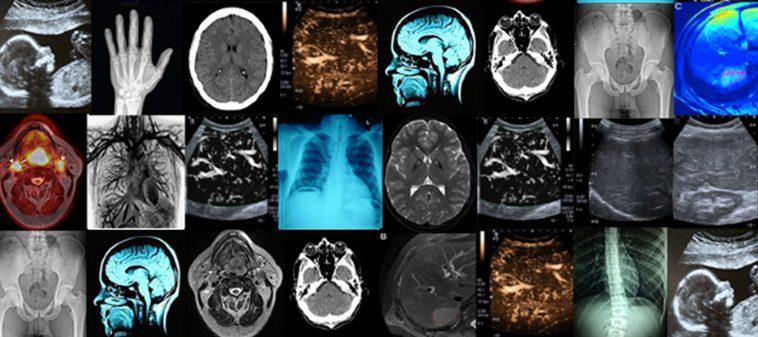

Registration is open for the 2023 Virtual @DukeRadiology Review Course!

Duke Radiology CME - Advanced Imaging in the Cayman Islands

Duke Radiology at RSNA 2022

National Radiologic Technology Week (NRTW) 2022 is here! NRTW is celebrated annually to recognize the vital work of imaging professionals across the nation.